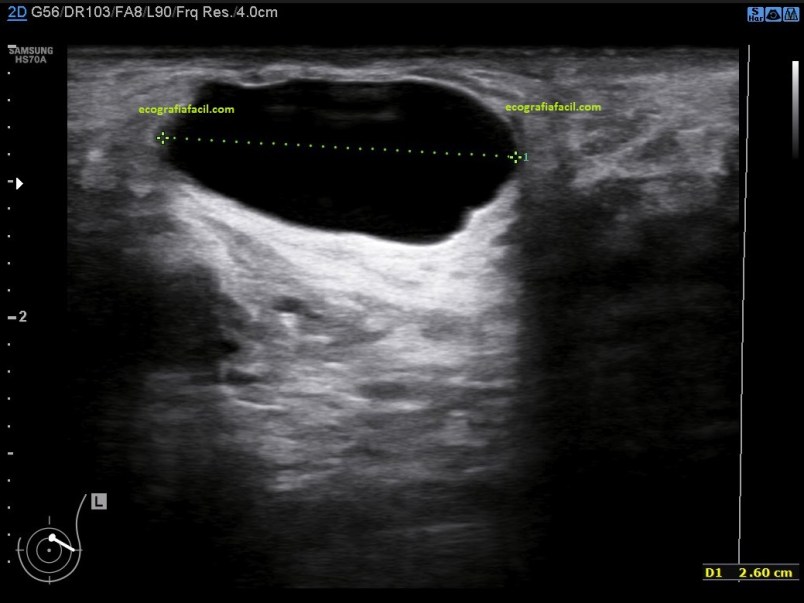

Esta semana subí una imagen a las stories de Instagram donde podíamos ver dos lesiones mamarias, dos nódulos, uno anecoico y otro hiperecogénico. Os pregunté qué veíais en la imagen, con dos opciones para contestar, la primera opción era que podían ser dos quistes, verdadera, y la segunda opción, un nódulo sólido y un quiste, la mayoría de las respuestas, por encima del 90%, escogisteis un nódulo sólido y otro quístico. Image 1.

Sabía que os iba a llevar al huerto esa foto, era difícil, en una sola foto podía ocasionar la duda más que razonable que el nódulo hiperecogénico fuera sólido, pero realmente, los dos nódulos eran quistes.

El anecoico no generaba dudas. El otro, todas. Y la pregunta que muchas me hicisteis era que cómo podía ser un quiste el nódulo hiperecogénico. Este post es aclaratorio y con las fotos lo vais a entender.

Ese nódulo de aspecto redondo, hiperecogénico de bordes definidos y buena transmisión es lo que en argot ecográfico de la mama llamamos quiste viejo. Te cuento… Los quistes sabemos que son estructuras más o menos ovaladas, bien definidas que transmiten muy bien, de borde bien definidos y lisos y anecoicas con refuerzo posterior.

Son quistes que cuando se extraen por PAAF lo que extraen las radiólogas suele ser una sustancia serosa, líquida, del color de un café muy aguado, son los típicos quistes mamarios…¿qué pasa? En ocasiones, con el paso del tiempo, estos quistes pueden modificar su aspecto interno y ecográfico, cambiando a una sustancia mucho más grasa y que cuando se evacúan tiene una aspecto mucho más denso, pastoso, muy graso, de color crema, siempre y cuando sea un quiste no complicado con pus o sangre u otras…esto es lo que conocemos «quistes viejos», y esto es justamente lo que le pasó a ese nódulo quístico de aspecto ecogénico, que era un quiste que había cambiado su aspecto.

Cambian su aspecto de este modo, normalmente son anecoicos siempre, luego empiezan a cambiar hasta que son mitad anecoicos, mitad ecogénicos, como la imagen 2 y luego son totalmente ecogénicos como el quiste ecogénico de la foto 1.

La radióloga puede tener dudas en algunas exploraciones, si por ejemplo es la primera exploración que se realiza la paciente apareciese este tipo de lesiones, entonces determinará ampliar con un estudio mediante intervencionismo o bien con control ecográfico, en este caso, no hizo falta pinchar el nódulo, vimos a ese quiste envejecer durante los controles que la paciente se realizaba regularmente y vimos cómo cambió de anecoico a hiperecogénico paulatina y lentamente año tras año, control tras control, primero siendo anecoico, luego parcialmente ecogénico y finalemente ecogénico por completo, siempre del mismo tamaño y colocado en la misma posición, por eso, en este caso no requirió análisis de Anatomía Patológica.